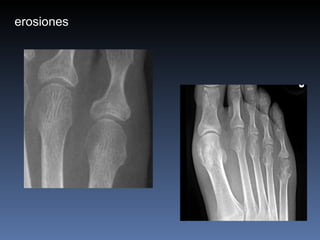

erosiones

Artritis Reumatoidea Muneca, MCFs, IFPs IFDs respetadas simetrica osteopenia Erosiones marginales Estrechez del espacio articular Edema fusiforme de tejidos blandos subluxaciones

Artritis Reumatoidea Muneca,MCFs, IFPs IFDs respetadas simetrica osteopenia Erosiones marginales Estrechez del espacio articular Edema fusiforme de tejidos blandos subluxaciones